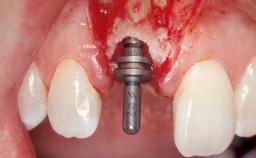

Late Placement of an Implant in a Maxillary Left Central Incisor Site

A 30-year-old female patient had lost tooth 21 and was referred to our clinic for consultation and treatment. Due to advanced apical infection, tooth 21 had been extracted two months earlier at another clinic and an acrylic-resin tooth had been bonded to the adjacent teeth. The patient desired implant treatment to avoid any damage to the adjacent natural teeth. While the patient had no history of any systemic disorder, she was a heavy smoker and exhibited medium to advanced periodontitis in the entire jaw. After the initial treatment to achieve a pocket probing depth of less than 4 mm and no bleeding on probing, a decrease in the height of the papillae mesial and distal to the extraction site and overall gingival recession were observed.